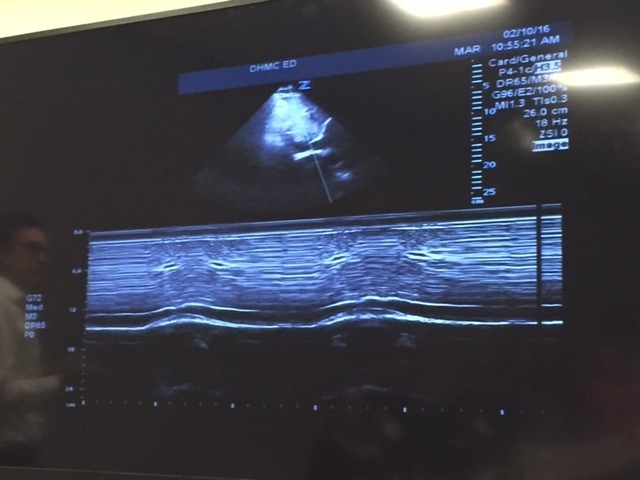

29 Photos